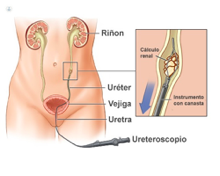

La prevalencia de la litiasis se sitúa entorno al 10-15 % de la población mundial. Existen diversos métodos de tratamiento, según el tamaño, localización y dureza de la litiasis, así como la anatomía de la vía urinaria del paciente. En algunos casos se puede optar por expectancia controlando las litiasis renales o si estas, están a nivel del uréter, esperando la expulsión espontánea de la litiasis, sin embargo, si esto no se consigue se puede valorar la litotricia extracorpórea (ondas externas que pulverizan o fragmentan la litiasis) o técnicas endourológicas mínimamente invasivas como la ureterorenoscopia o nefrolitotomía percutánea, dejando las técnicas laparoscópicas o robóticos para casos seleccionados o complejos, mientras que el papel de la cirugía abierta actualmente ha quedado relegada, debido a los beneficios de las técnicas mínimamente invasivas que ofrecen menos morbilidad y gran efectividad.

En caso de optar por técnicas endourológicas, estás tienen la ventaja de la escasa morbilidad y recuperación rápida por parte del paciente, ya que se usan instrumentos muy finos para llegar a la o las litiasis y mediante diversas fuentes de energía se consigue fragmentar y/o pulverizarlas. Dentro de las diversas fuentes de energía el láser es la más versátil, ya que se transmite mediante fibras muy pequeñas de diversos calibres, que pueden pasar por los diversos canales de trabajo y acoplarse a instrumentos rígidos y flexibles llegando a localizaciones complejas, lo cual no se puede conseguir con otras fuentes de energía (energía mecánica o ultrasónica), además la energía puede ser modificada para conseguir un mejor efecto sobre la litiasis según su dureza, ya sea fragmentándola y posteriormente retirarla con pequeñas cestas o pulverizarlas para conseguir la expulsión espontánea por parte del paciente. La efectividad del láser ha sido reconocida por diversas sociedades de urología catalogándola como la mejor herramienta para el tratamiento de las litiasis renales.